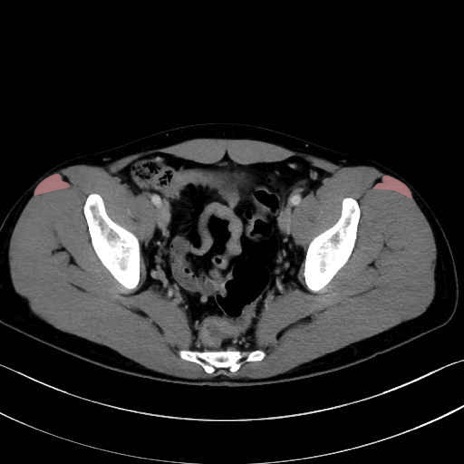

大腿筋膜張筋 (Tensor fasciae latae)